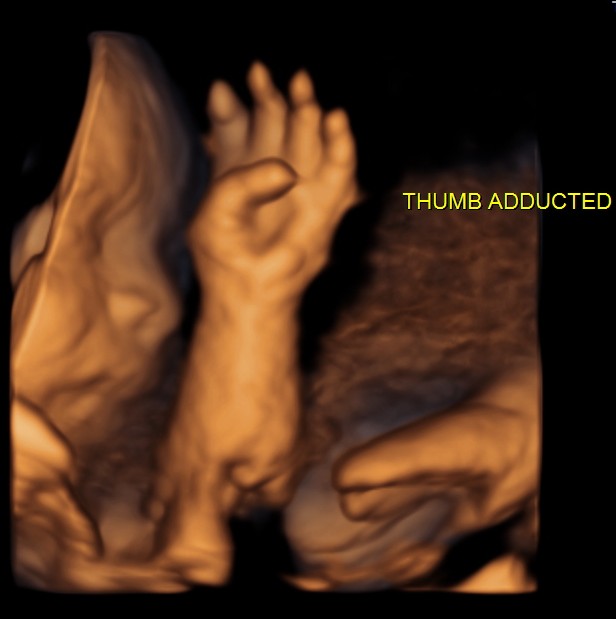

right hand with persistent adducted thumb

persistently adducted left thumb

CDH ADD THUMB_34according to radiology review manual , adducted thumb = short 1st metacarpal + phalanges and is diagnostic of trisomy E syndrome ( 16 to 18 )

flexed and ulnarly deviated  and the thumb is adducted. This position is constant during the examination and is strongly suggestive of trisomy 18